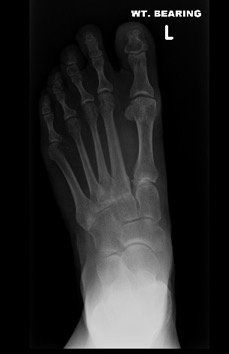

Midfoot arthritis refers to arthritis in the middle part of the foot. There are a number of joints that make up this part of the foot and arthritis in this area presents with degenerative changes. Degenerative changes are depicted by pain in the area, instability of the joint, narrowing of the joint space, osteophytes or bone spurs, cystic areas within the bone, damage to the joint cartilage, and laying down of extra bone.

Surgery for midfoot arthritis ranges from simple to more complex procedures. Surgery may involve a “clean-up” of the joint by removing damaged cartilage and bone spurs, resection of a part of the joint, fusion (stiffening) of one or more joints. Medical imaging, such as x-rays and MRIs are usually obtained prior to surgery to determine the extent of the injury and to plan for the proposed surgery.